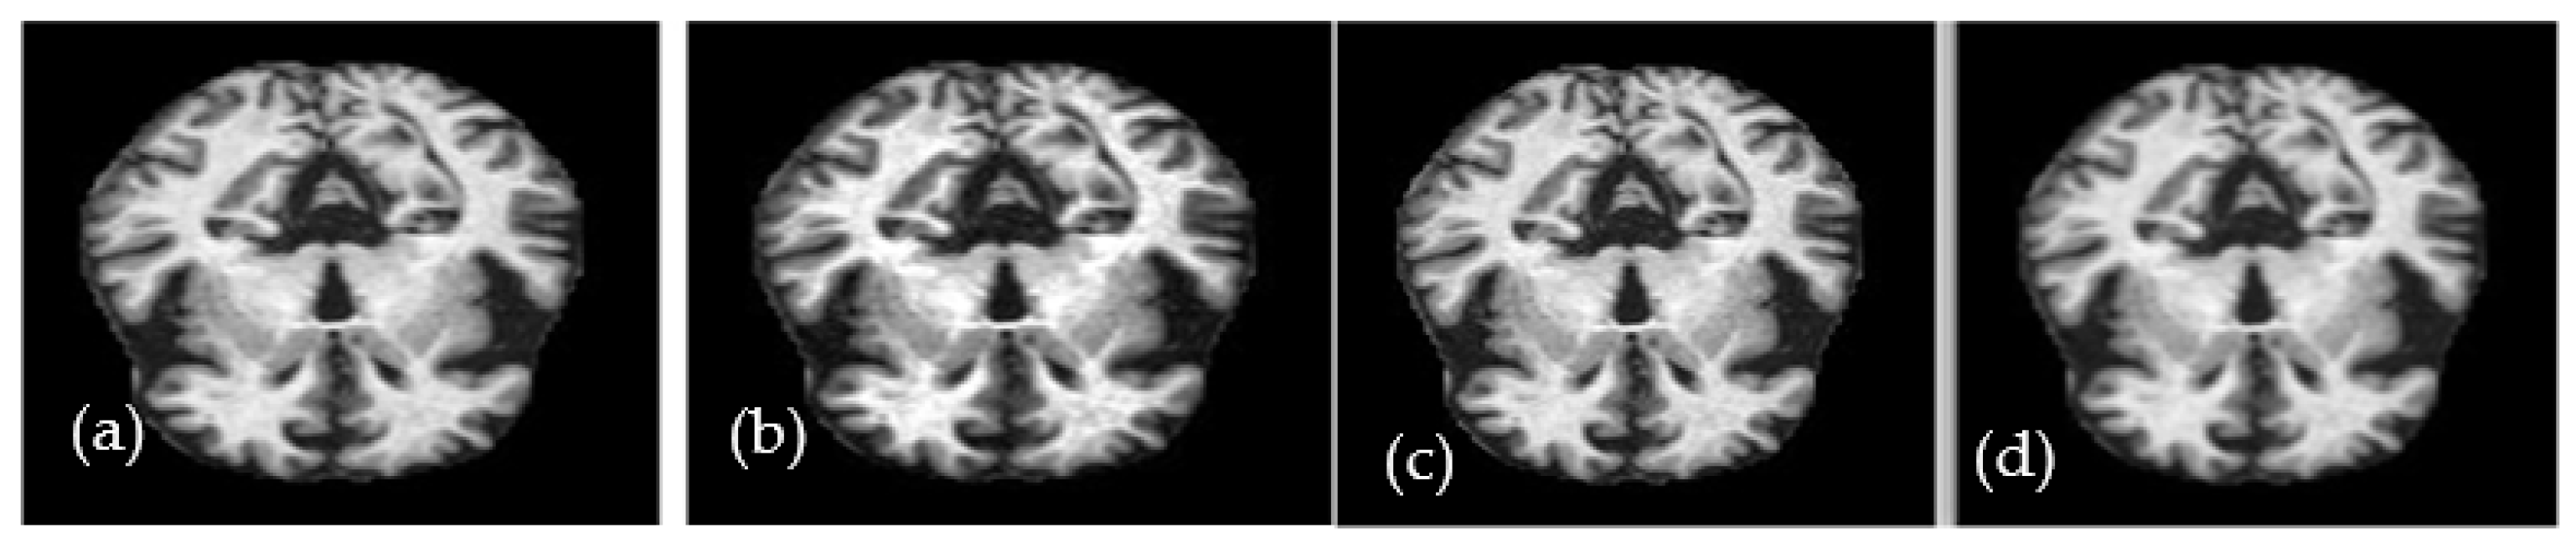

A researcher developed the ALZ dataset [60], which consists of four stages. The collection includes MR images with various resolutions that were gathered from various websites. The hybrid dataset that was used in this investigation was made available online. The collection consists of 5000 JPG-formatted images in total. This dataset was increased by a data augmentation technique which is explained in the coming subsection. In this study, 10-fold cross-validation tests are applied to produce various validation/testing/training ratios. Classes made up of the four phases of ALZ make up the dataset. These stages are mildly (MID), moderately (MOD), normally (NOD), and very mildly (VMD) demented. Furthermore, no comprehensive information was provided regarding the patients from whom the dataset was compiled. Because of this, the homogeneity or heterogeneity of the images in the dataset is unknown. Figure 1a displays examples of MRI images that correspond to the dataset’s classes, and Figure 1b visually displays those sample images of ALZ disease stages.

Figure 1.

(a) Distribution of 4 different classes and (b) a sample image in the selected dataset.